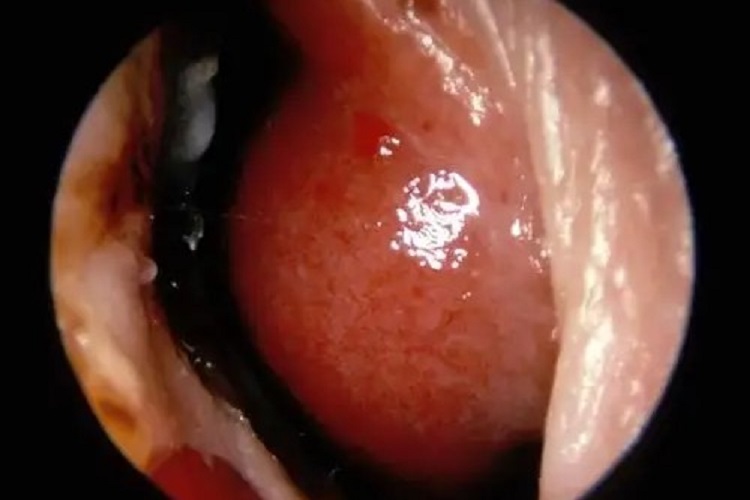

白血病患者可能存在出血倾向,出血点可能在机体任意部位,如皮肤表面可有出血点、瘀斑,口腔、鼻腔、消化道等部位黏膜也会有出血点。除此之外,内脏、颅内等也可能有出血,严重者可由于颅内出血而导致死亡。